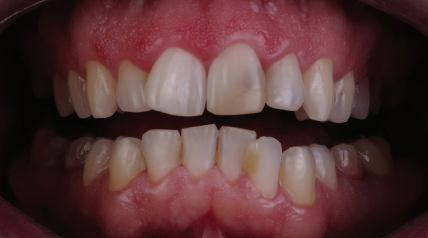

Пациентът постъпи в клиниката с молба за тотална рехабилитация на усмивката. Той не харесваше централ ните си резци, които според него бяха твърде къси и квадратни. Имаше раз стояние от медиално и дистално на латералните му резци. Друго сериоз но оплакване бе свързано с металоке рамичната корона на зъб 12, която бе жълтеникава и неестетична, като цяло не харесваше вида на венците си и както самият той се изразяваше, „вижда се прекалено много от венците при усмивка“.

Една седмица след препарацията на зъбите и циментирането на цирко ниевото кепе бяха изработени 12 IPS Empress Cad Multi фасети. Макро- и микротекстурата на фасе тите бяха направени на ръка, след кое то бяха нанесени 3D характеризации с боички, а полирането отново бе напра вено ръчно, за да им се придаде естест вен и естетичен вид. Предизвикателството тук беше короната да има същите оптични характеристики като тези на остана лите зъби при естествена светлина, през поляризационен и флуоресцентен филтър. 3D принтерът бе Fromlabs, софтуерът за фрезоване – Mill Box, а фрез апаратът –imes icore CORiTEC 350i. В крайна сметка постигнахме ес тествен вид на усмивката с натурал на зъбна морфология при изцяло диги тален протокол, при който дизайнът бе направен първоначално и през всич ки етапи на лечението се придържахме към него до самия край Излишно е да отбелязваме, че всички сме удовлетворени от постигнатото! Преди След Победител в категория „Клиничен случай с изцяло дигитален протокол“ в конкурса „Усмивка на годината 2022“

11Dental Tribune Bulgarian Edition / октомври 2022 г. Преди лечението Фиг. 1 Фиг. 2 Фиг. 3 Фиг. 4 Фиг. 5 Фиг. 6 Фиг. 7 Фиг. 9 Фиг. 10 Фиг. 11 Фиг. 8 Фиг. 12 Фиг. 13